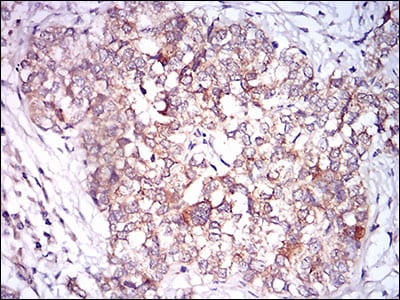

![CAMK2G Mouse mAb[63190]](https://img1.dxycdn.com/p/s14/2025/0922/032/2994483504192699691.jpg)

Immunohistochemical analysis of paraffin-embedded human prostate cancer tissues using CAMK2G mouse mAb with DAB staining.